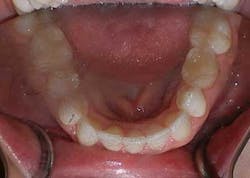

A 27-year-old female presented with a chief complaint of crowding on the upper and lower arches. Upon evaluation, it was noted that the patient had 2 mm and 4.5 mm of maxillary and mandibular arch length deficiency respectively, a missing lower left second bicuspid with primary tooth still present, small upper lateral incisors, cross-bite of the lower right canine, and lower midline shift to the right of 2 mm. (Figs. 1-8)

Figs. 1-8